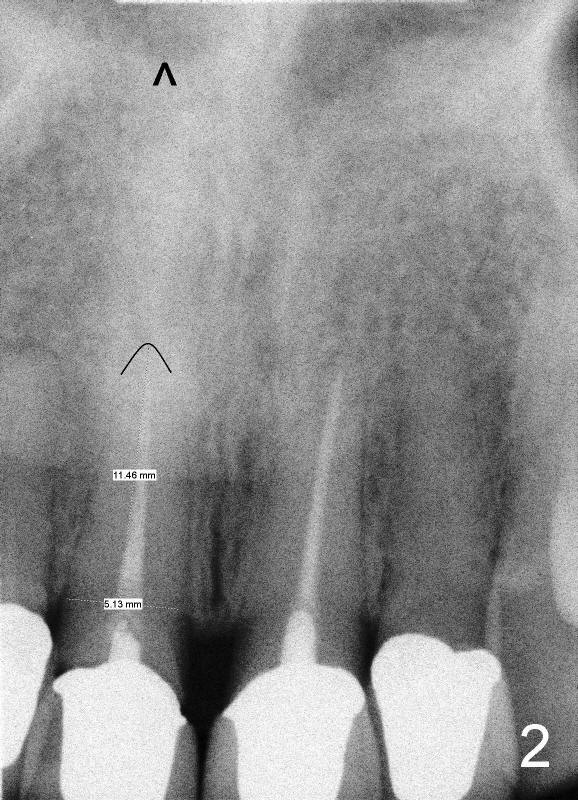

四十四岁女病人上颌中切牙突然断裂(图一:8),经过讨论,她同意植牙。由于根尖(图二黑线轮廓)上方骨头很多(箭头:鼻底),适合立刻植牙。牙根长度十一毫米左右,宽度约五毫米,准备植入直径五毫米植牙。拔牙后使用两毫米钻头,深度二十毫米(图三从颊侧牙龈缘算起),超过牙槽窝底部接近七毫米,所以植牙至少有七毫米新骨支持,将非常稳定。然后逐步使用2.5, 3.0, 和3.5毫米钻头,同一个深度,边钻边注意钻头(图四:D)近远中(图四)以及颊舌侧(图五)方向。